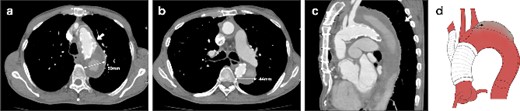

A 62-year-old male presented at the previous hospital with left hemiplegia. Computed tomography (CT) detected an aortic dissection with malperfusion of the right brachiocephalic artery, necessitating a referral to our institution. Preoperative CT showed the primary entry tear in the distal aortic arch and a patent false lumen. A total arch replacement was successfully performed using the fenestrated FET technique. The surgical procedure involved median sternotomy, establishment of extracorporeal circulation with right atrial drainage and perfusion via right axillary artery, circulatory arrest at 28°C and selective cerebral perfusion to perfuse all cervical vessels. Myocardial protection was provided by retrograde cardioplegia. Following resection of the aorta at zone 1, FET was inserted and deployed into the aorta, perfusing blood from the femoral artery. Fenestration of the graft at the ostium of the second and third cervical branches was performed. A U-shaped graft was placed around cervical branches, and three 4-0 polypropylene U-shaped sutures were roughly placed to fix the open stent graft, leaving some gaps between the sutures. Subsequent procedures included anastomosis of a four-branch graft to the distal aorta, reconstruction of the brachiocephalic artery and proximal anastomosis. Postoperative contrast-enhanced CT on day 5 showed no endoleak and favorable remodeling of the descending aorta (Fig. 1). However, after 6 months, follow-up CT detected a fenestration-related endoleak and an enlarged aortic arch (Fig. 2), prompting reoperation. The reoperation involved median re-sternotomy, establishment of extracorporeal circulation with right femoral vein drainage and perfusion via an 8-mm graft anastomosed to the left axillary artery, circulatory arrest at 28°C, and selective cerebral perfusion to perfuse all cervical vessels. Upon opening the artificial graft, it was observed that the stent graft had some gap between fixed U-sutures and had become detached from the aorta, revealing a small entry adjacent to it, which communicated with the false lumen. The left subclavian artery (LSCA) was ligated, and the left common carotid artery was transected at its origin and sutured. An open stent was inserted distally, followed by placement of a felt strip and a 4-0 running suture. Subsequent procedures included anastomosis of a four-branch graft to the distal aorta, reconstruction of the three cervical branches and proximal anastomosis. The surgery was completed without complications. Postoperative contrast-enhanced CT on day 5 revealed resolution of the endoleak with no blood flow into the false lumen of the arch. Follow-up CT 3 months after discharge revealed favorable remodeling of the aortic arch (Fig. 3).

CT 3 months after redo surgery reveals no endoleak and no flow in the false lumen, and remodeling of the aorta at the levels of the aortic arch (a) and the carina of the trachea (b). Sagittal image (c). An illustrative diagram (d) shows the postoperative schema.